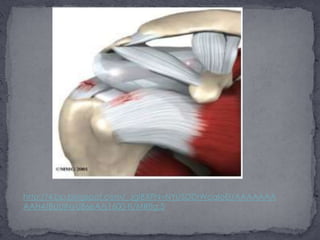

El llamado "Manguito rotador" en una unión de 4 tendones de 4 músculos que se encargan en forma conjunta de abrir el hombro "abducción" y de realizar rotaciones y estos están situados por arriba de la cabeza del humero pero por debajo de hueso de acromion, como se ve en esta imagen.http://2.bp.blogspot.com/_JgiBXPNvNYI/SDDrD8aIoCI/AAAAAAAAAHo/Ew2KdKHEU_o/s1600-h/MRfig.2

El llamado "Manguito rotador"en una unión de 4 tendones de 4 músculos que se encargan en forma conjunta de abrir el hombro "abducción" y de realizar rotaciones y estos están situados por arriba de la cabeza del humero pero por debajo de hueso de acromion, como se ve en esta imagen.http://2.bp.blogspot.com/_JgiBXPNvNYI/SDDrD8aIoCI/AAAAAAAAAHo/Ew2KdKHEU_o/s1600-h/MRfig.2